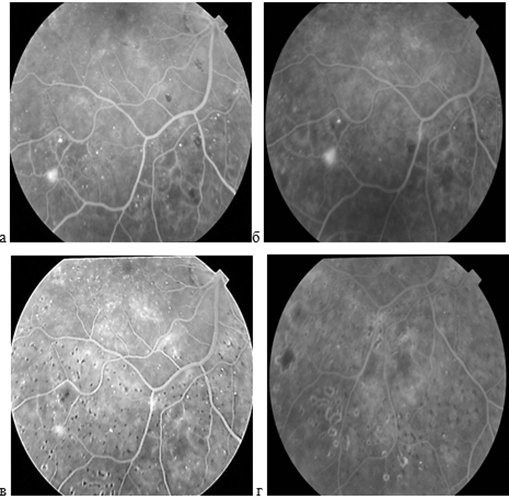

В качестве примера приводятся цветные фотографии глазного дна и ангиограммы обоих глаз пациента П. (рис. 2). На левом глазу неоваскуляризация видна как на фотографии, так и на ангиограммах. На правом глазу мелкая неоваскуляризация не видна на фотографии и выявляется только на ФАГ.

Рис. 2. Цветная фотография глазного дна левого (а) и правого глаза (в) и артериовенозная фаза ФАГ левого глаза (б) и правого глаза (г) больного П.

Составлено авторами по результатам данного исследования